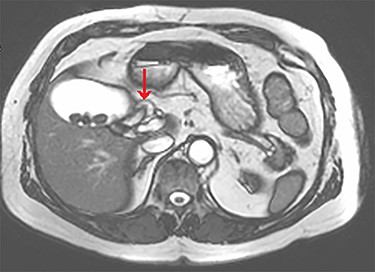

The tubular structure was remote from the porta hepatis with one lumen. It was located within the distal gallbladder fossa. Inspection of the gallbladder demonstrated an opening at the same orientation and of the same calibre as this tubular structure, raising suspicion for a duplicated cystic duct. Probing the source of the bile leak confirmed a single lumen. The capacity to perform IOC was not available at the time of the operation. A review of the patient’s prior imaging was performed. Recent cardiac magnetic resonance imaging (MRI), while not dedicated magnetic resonance cholangiopancreatography (MRCP), provided adequate views of the liver, gallbladder and biliary tree to demonstrate the suspected anomaly. On these images, two structures were seen to be connecting the gallbladder to the biliary tree. One duct was observed at Hartmann’s pouch, while a second connected to the gallbladder body (Fig. 1, Fig. 2). The images confirmed suspicion of a duplicated cystic duct and the decision was made to clip the lumen. The cholecystectomy was completed and a drain placed in the gallbladder fossa.

Axial view of the liver and gallbladder from a cardiac MRI showing a tubular structure entering the gallbladder at the level of the body in keeping with an accessory cystic duct (highlighted by the arrow).